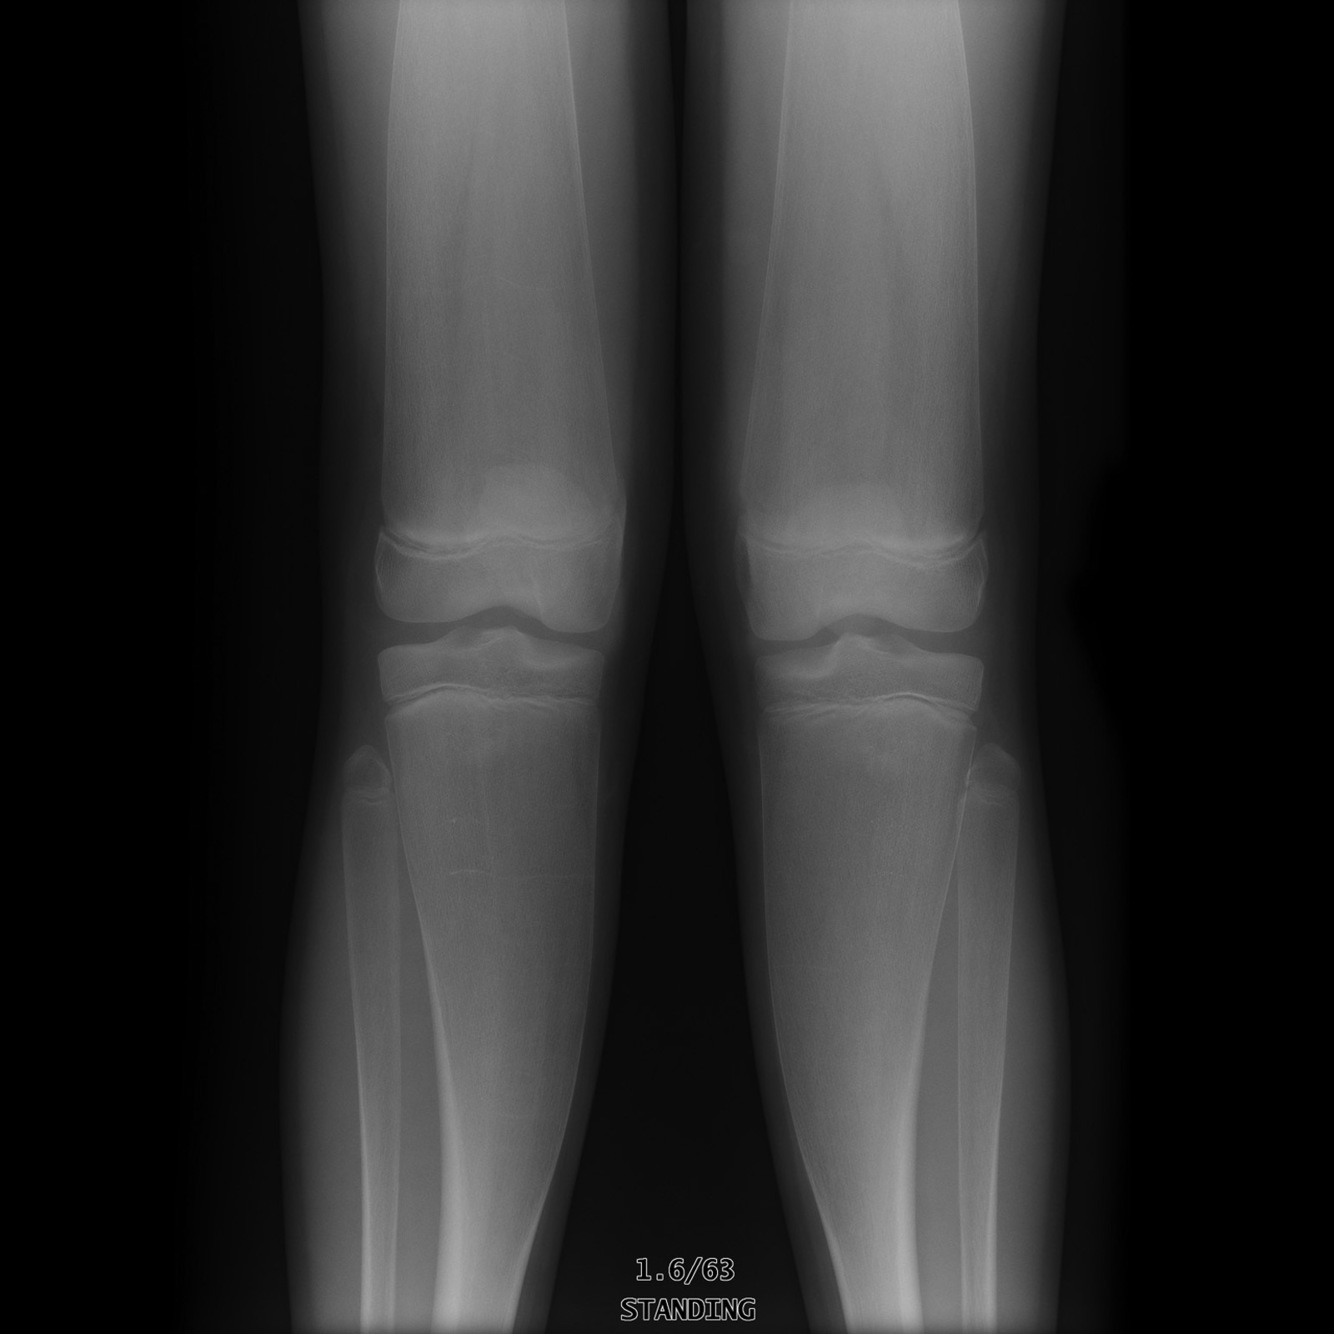

Causes of this appearance

A

Lead GNOMES

Lead: lead poisoning

G: Gaucher disease

N: Niemann-Pick disease

O: osteopetrosis, osteochondromatosis

M: metaphyseal dysplasia (Pyle disease) *CASE 1* and craniometaphyseal dysplasia

E: ‘ematological, e.g. thalassaemia

S: Sickle cell

R: Rickets (*case 2*)

Erlenmeyer flask deformity

Erlenmeyer flask deformity (EFD), also known as metaphyseal flaring, refers to a radiographic appearance typically on a femoral radiograph demonstrating relatively reduced constriction of the diaphysis and flaring of the metaphysis as a result of undertubulation.

The name refers to the resemblance to a flat bottomed titration flask used by chemists, (known as a conical flask in British English.)

It has been classically used with reference to the distal ends of the femora, however it is also seen in the proximal humeri, tibiae, and the distal radii and ulnae 4.